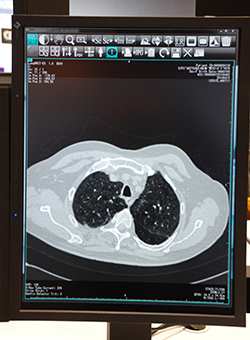

iRad-QAで検像された画像は,PACSであるiRad-IAのサーバに保存される。読影には,DICOMビューワの「eFilm Workstation」が用意されている。eFilm Workstationは,MPRといった画像処理や心胸郭比計測などの機能を搭載している。